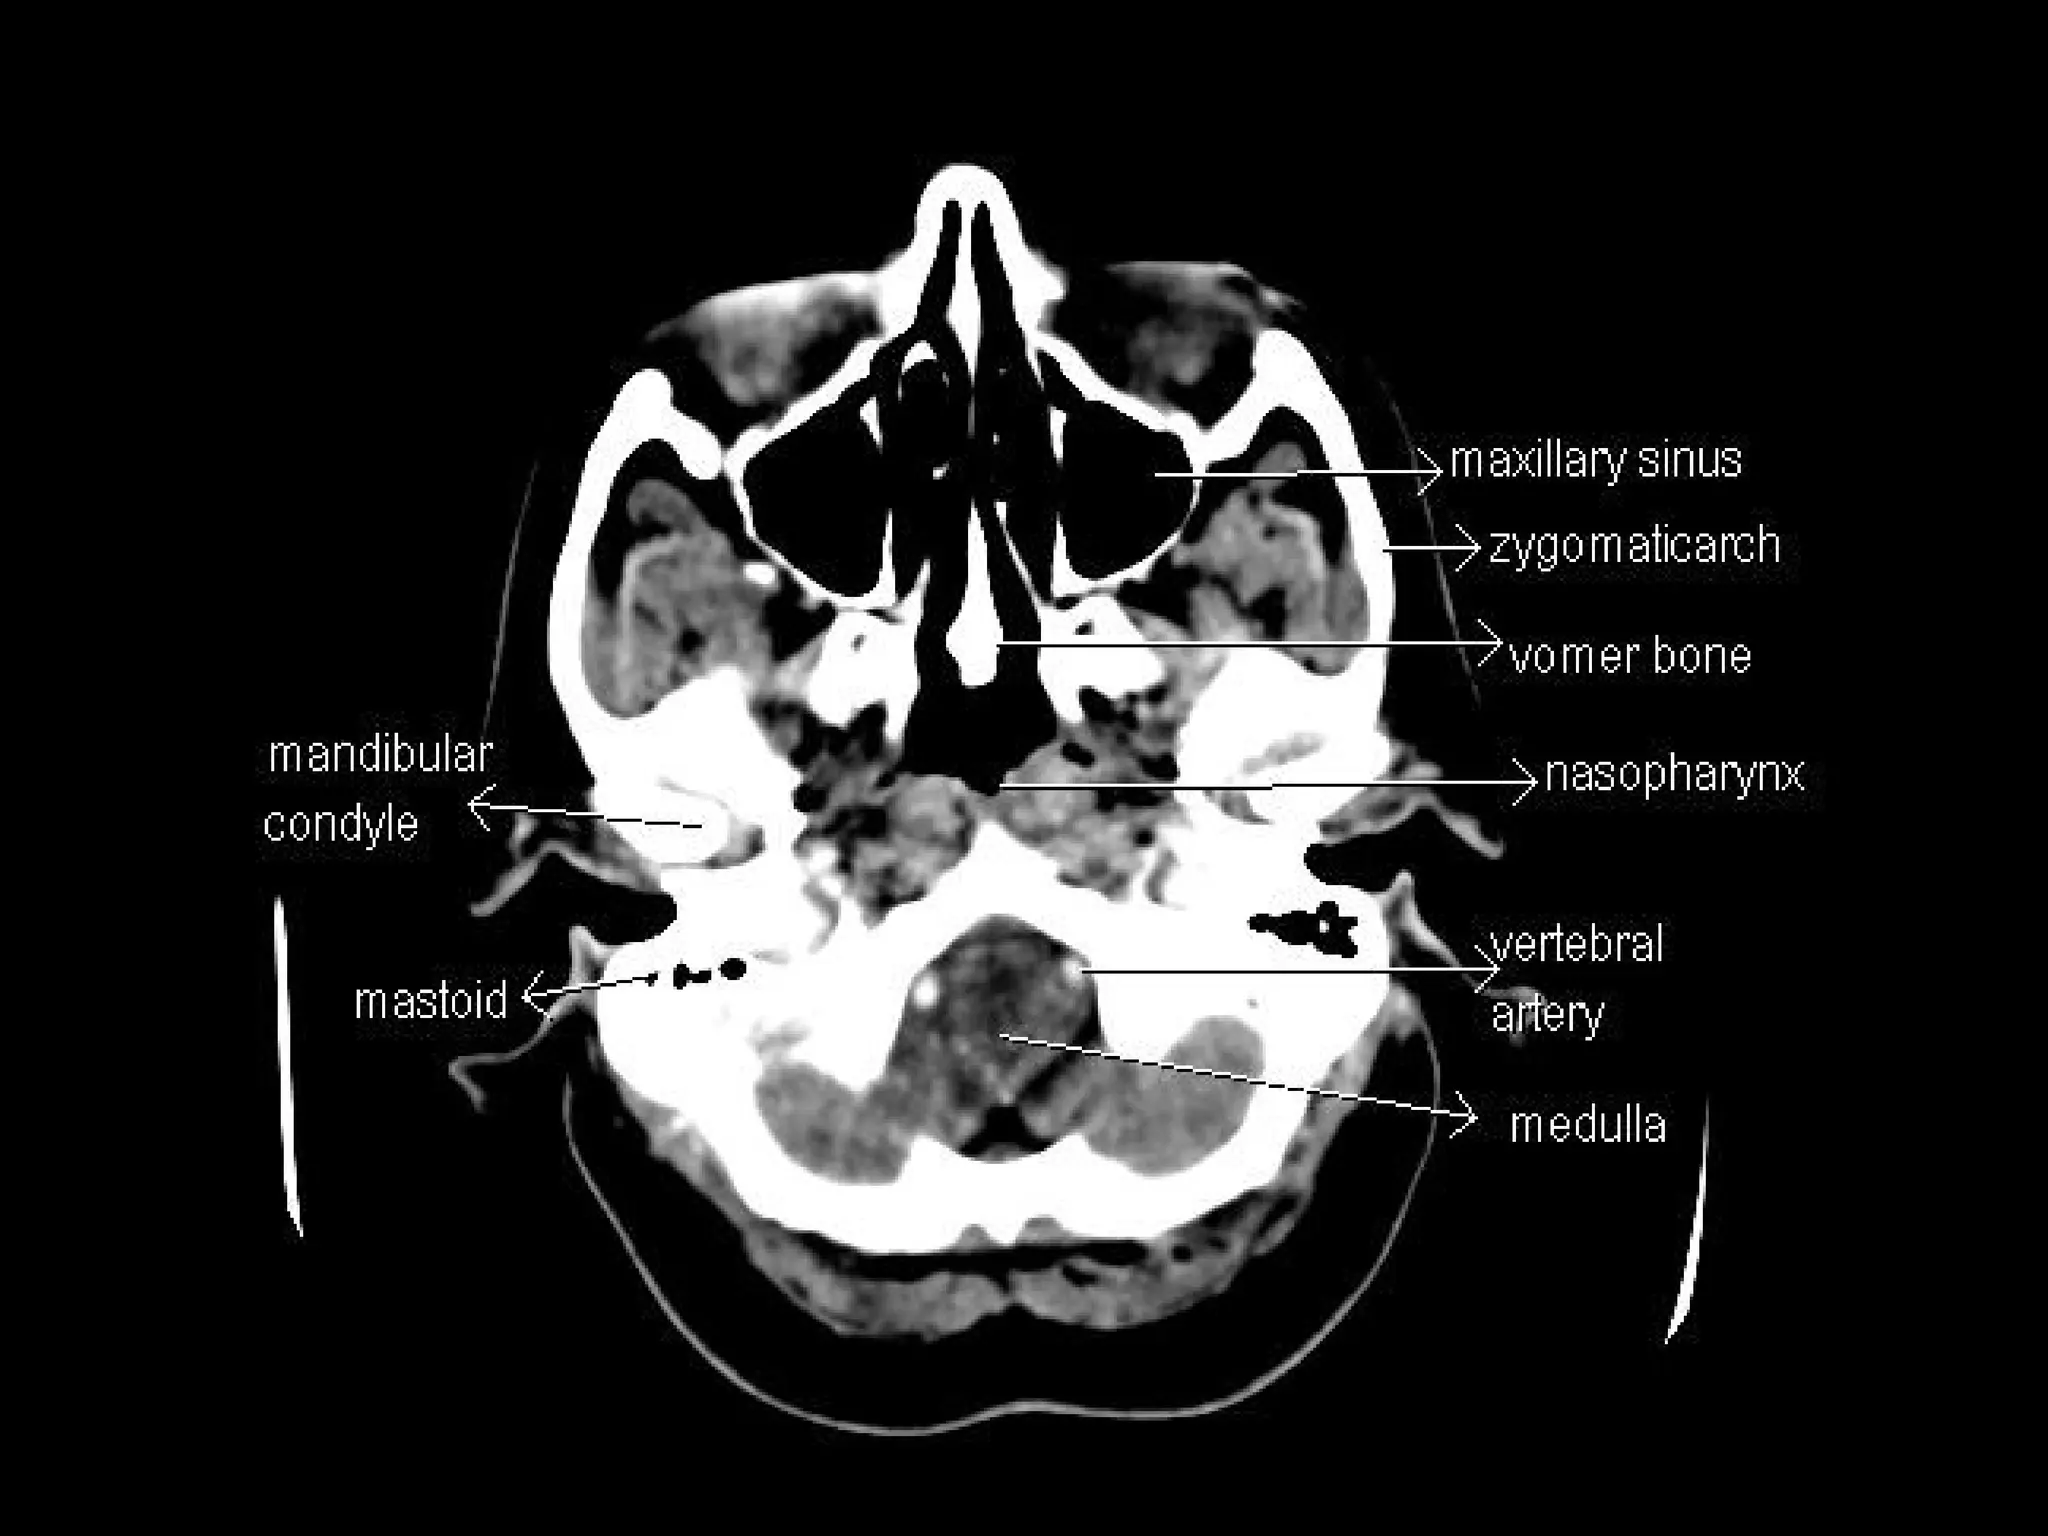

Radiographers are medical professionals who perform diagnostic imaging examinations and procedures to help physicians diagnose and treat diseases. They work under the supervision of radiologists to operate X-ray, CT, MRI, ultrasound and other medical imaging equipment and must have a strong understanding of human anatomy and pathology. Radiographers are responsible for correctly positioning patients, ensuring proper imaging techniques are used, and evaluating the quality of the resulting images.